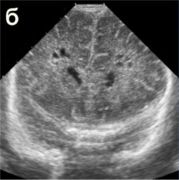

| Перивентрикулярный отек а, б, в, г - ребенок 2-х суток жизни с вдавленным переломом левой теменной кости. Структуры головного мозга симметричны. Сканирование во фронтальной и саггитальной плоскостях выявляет повышение эхогенности в перивентрикулярных областях без эхо-признаков других патологических изменений. При ДГ - невыраженное повышение показателей периферического сопротивления (спазм сосудов) д, е, ж - ребенок 1-х суток жизни от травматичных родов, парез Эрба слева, петехиальные кровоизлияния на лице, кровоизлияния в склеры, оценка по Apgar - 3-5 баллов. Определяется значительное повышение эхогенности в перивентрикулярной области, при ДГ - снижение показателей периферического сопротивления (парез сосудов). Перивентрикулярная лейкомаляция

|  |  | | а, б, в - фронтальные. |  |  | г, д - саггитальные сканы в разных плоскостях, В-режим. Определяются зоны перивентрикулярной лейкомаляции с обеих сторон. | Перивентрикулярное кровоизлияние в стадии псевдокисты